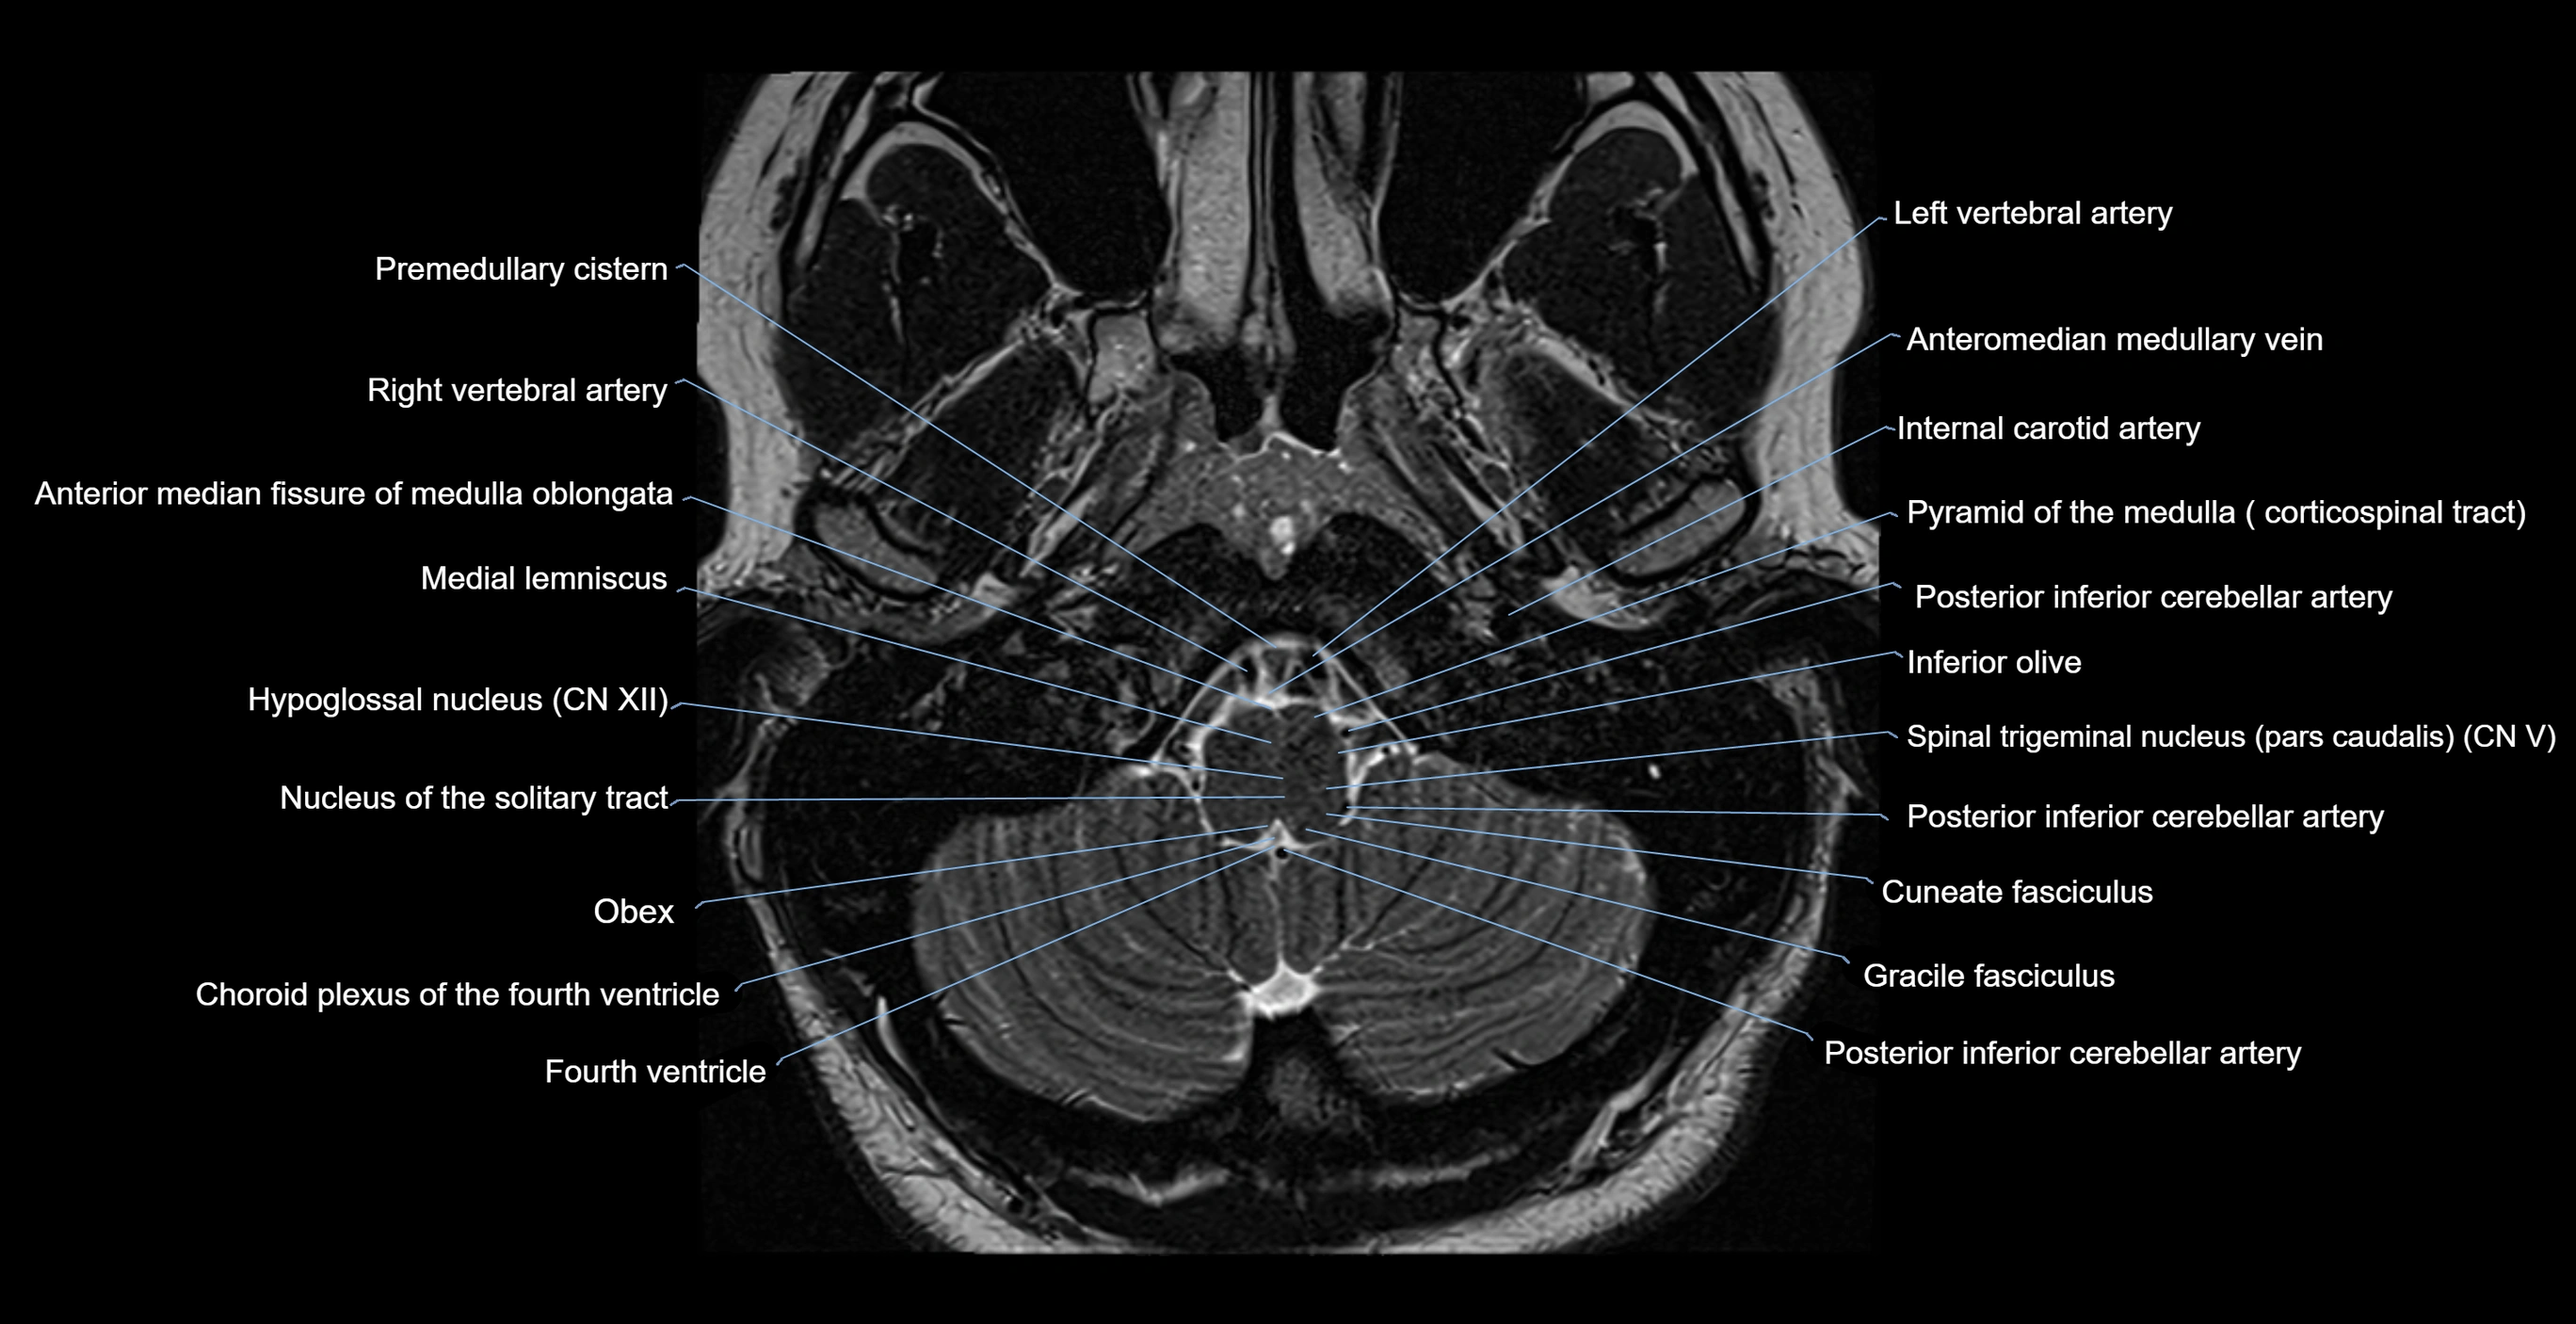

MRI images